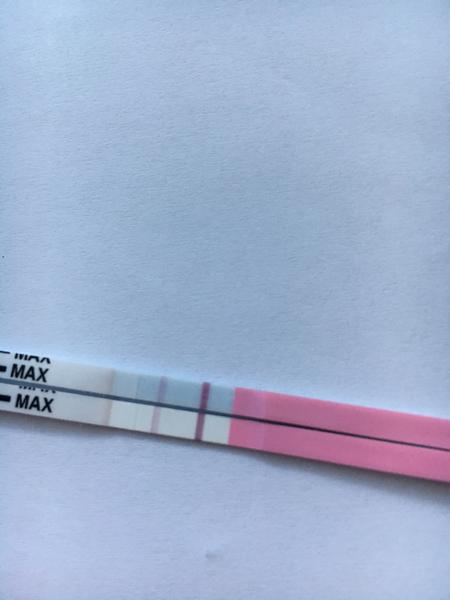

ahojte babule, mam taku otazku...mate skusenost ze pocas 3 dni vam nesilnela druha ciarka na teste ale bola rovnaka???ako duch????

@lenusa20 ahoj, ten posledný test je podľa mňa chybný. Nie je možné aby si po štyroch testoch ktoré krásne silneli zrazu mala čistý test. Okrem toho tieto testy (ten posledný) robí kanáliky dievčatám ktoré tehotné niesu.. Za mňa by som ti odporučila obyčajný pepino test, alebo v tescu predávajú také úplne lacné testy sú citlivosť 25ml ale za mňa odporučujem alebo potom rovno digi test clearblue, ktorý ti ukáže aj dobu od oplodnenia. Veľa šťastia a krásne // čiarky prajem 😊

@zuzuliena1 @nivea777 Ten 10 je teraz pred polhodinou robeny. Mne tiez hlava nekapca, ze 20tkove uz naznacovali od 8DPO a 10tkovy hoci teraz robeny a zrazu nic!!! Skusim zajtra rano este a uvidim ci ta mrcha nakoniec nepride...a uvidim co sa bude diat do piatku a ked nic, tak skocim k dr. na vysetrenie :/

@lenusa20 Tak daj vediet zajtra z ranného ako si dopadla je to naozaj zaujímavé ze ti to 10 neukázal :-\

@tshirt aj mne sa to javí ako dúšik, testuj z ranneho mocu alebo skus az o 2 dni.

@lenusa20 a ten posledný uz ale nie z ranného ci ? A kolk